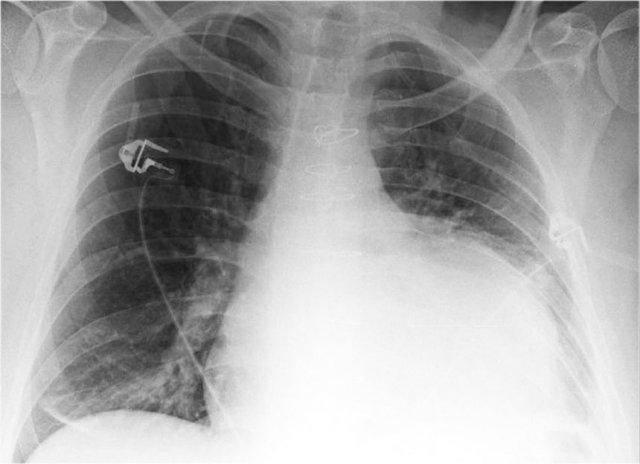

Bệnh nhân nam 70 tuổi nhập viện sau khi ngã xuống cầu thang, than phiền đau dữ dội vùng hông phải.

Kết quả hình ảnh

- Trên phim X-quang ngực tư thế thẳng (PA), không thấy hình ảnh ngón thứ năm bên phải.

- Trên tư thế nghiêng, có hình ảnh tăng tỷ trọng chiếu lên vùng cột sống ngực dưới.

Chẩn đoán của bạn là gì?

Các dấu hiệu phù hợp với xẹp phổi thùy dưới phải.

Trên tư thế thẳng (PA), lưu ý bờ tim phải có hình dạng bất thường. Động mạch phổi liên thùy phải không được nhìn thấy — do nó không được bao quanh bởi nhu mô phổi thông khí, mà thay vào đó là thùy dưới phải bị xẹp, nằm kề cạnh nhĩ phải.

Trên phim chụp kiểm tra, thùy dưới phải đã nở lại và hình ảnh xẹp phổi đã hồi phục.

Điều này gợi ý rằng xẹp phổi nhiều khả năng là do giảm thông khí sau chấn thương kèm theo nút nhầy.

Cũng ghi nhận trên phim kiểm tra là sự tái xuất hiện của ngón thứ năm bên phải (mũi tên đen) và sự phục hồi bờ tim phải bình thường (mũi tên trắng), xác nhận thùy dưới đã nở lại.